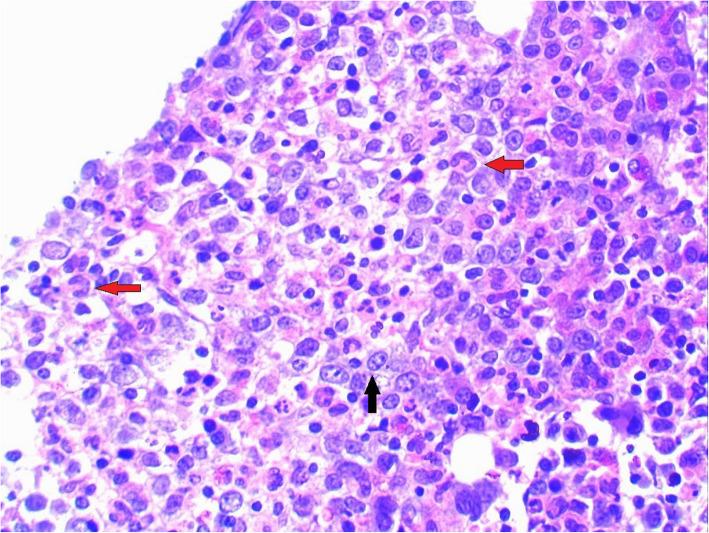

A 4-year old Sri Lankan boy presented with gradually worsening difficulty in walking for two weeks duration. He was previously diagnosed and managed as having non-transfusion-dependent α-thalassaemia based on the presence of hypochromic microcytic anaemia, haemoglobin H inclusion bodies in the blood film and compound heterozygous α-thalassaemia genotype with a gene deletion. However, his transfusion requirement increased over the past three months and he gradually lost his motor developmental milestones during two weeks before admission. The neurological examination revealed generalised hypotonia, exaggerated knee jerks and extensor plantar response. His complete blood count showed pancytopenia, and bone marrow biopsy revealed megaloblastic changes. Serum vitamin B and red blood cell folate levels were low. MRI revealed sub-acute combined degeneration of the spinal cord with characteristic 'inverted V sign'. Urine analysis showed non-nephrotic range proteinuria. The diagnosis of Imerslund-Gräsbeck syndrome was made due to the presence of non-nutritional vitamin B deficiency and asymptomatic proteinuria. He showed a rapid haematological and neurological improvement to intramuscular hydroxocobalamin.

一名4岁的斯里兰卡男孩出现行走困难逐渐加重,持续两周。他之前因存在低色素小细胞贫血、血片中的血红蛋白H包涵体以及具有基因缺失的复合杂合α地中海贫血基因型,被诊断为非输血依赖型α地中海贫血并接受相应治疗。然而,在过去三个月里他的输血需求增加,且在入院前两周逐渐失去运动发育里程碑。神经系统检查显示全身肌张力减退、膝反射亢进和伸性跖反射。他的全血细胞计数显示全血细胞减少,骨髓活检显示巨幼细胞改变。血清维生素B和红细胞叶酸水平较低。MRI显示脊髓亚急性联合变性,具有特征性的“倒V征”。尿液分析显示非肾病范围蛋白尿。由于存在非营养性维生素B缺乏和无症状蛋白尿,诊断为伊默斯伦德 - 格里斯贝克综合征。他对肌肉注射羟钴胺素表现出快速的血液学和神经学改善。